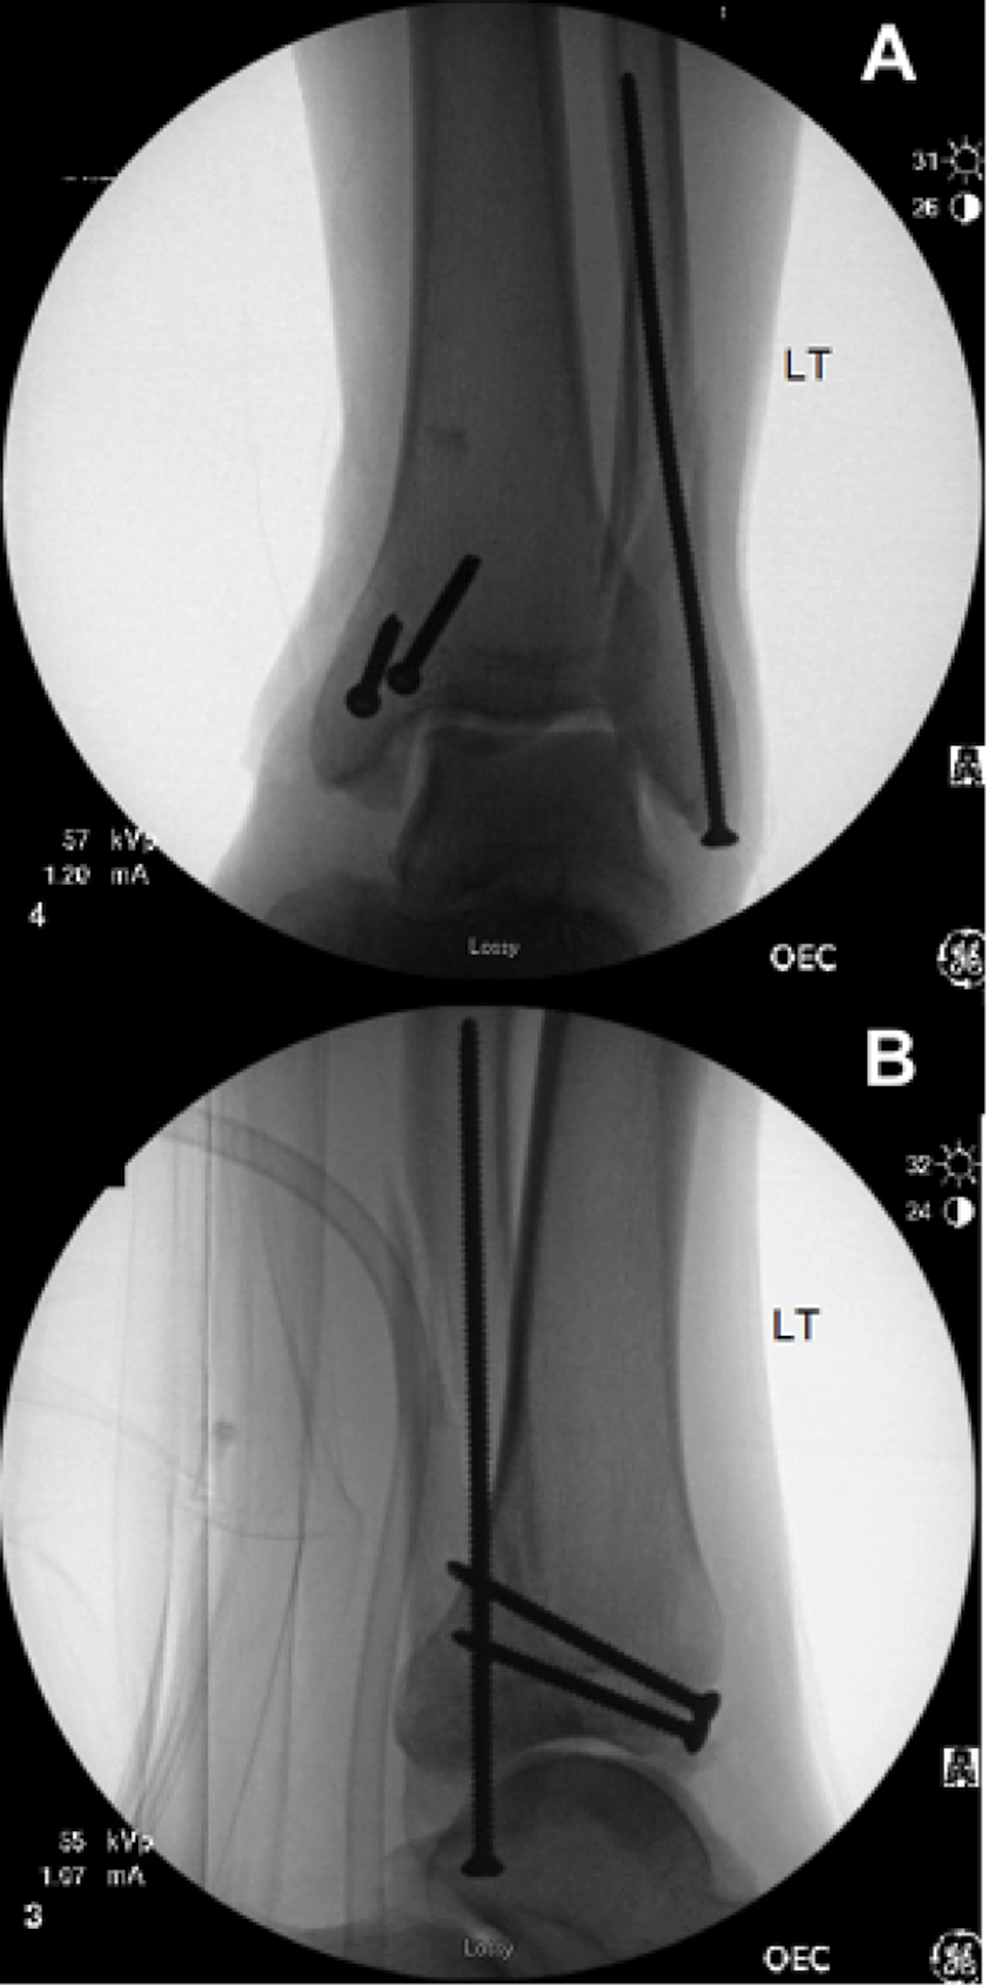

Minimally Invasive Treatment of Ankle Fractures in Patients at High

Minimally Invasive Treatment of Ankle Fractures in Patients at High Fracture Blister Treatment Fracture treatment should ideally take into account two major considerations, the treatment of the bone. Treatment with dressings infused with silver has been shown to speed up recovery time from. fracture blister complicate approximately 3% of fractures that require hospital treatment. awareness of fracture blisters pathophysiology and their management options are crucial for orthopaedic. fracture blisters are. Fracture Blister Treatment.